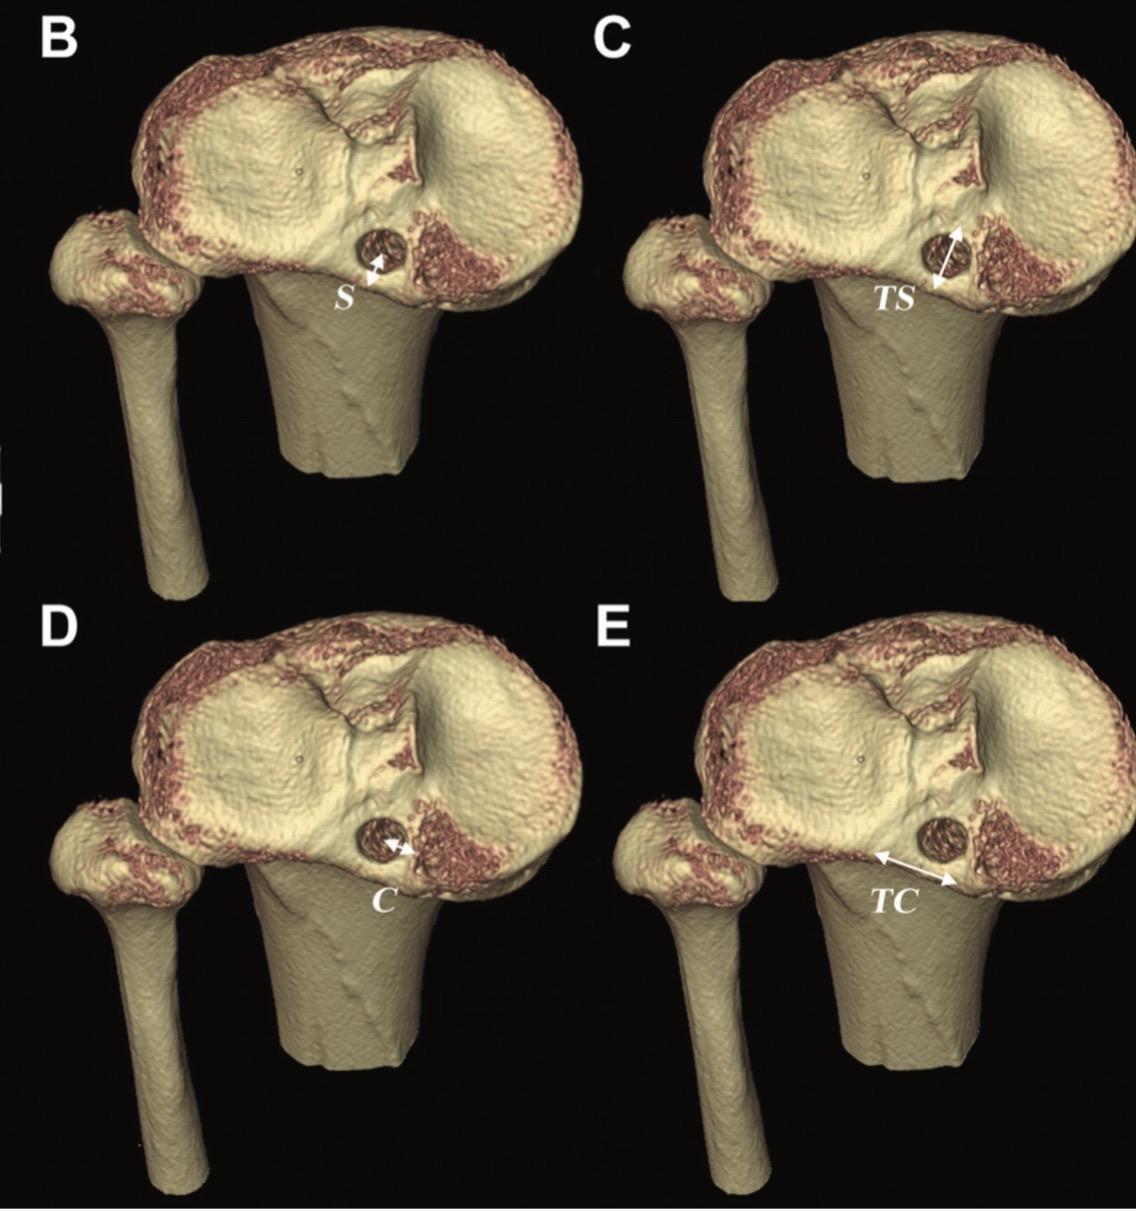

后交叉韧带重建。后交叉韧带(PCL)重建手术中,适当的隧道位置、隧道角度和移植物角度对于维持PCL移植物的稳定性和机械性能至关重要!